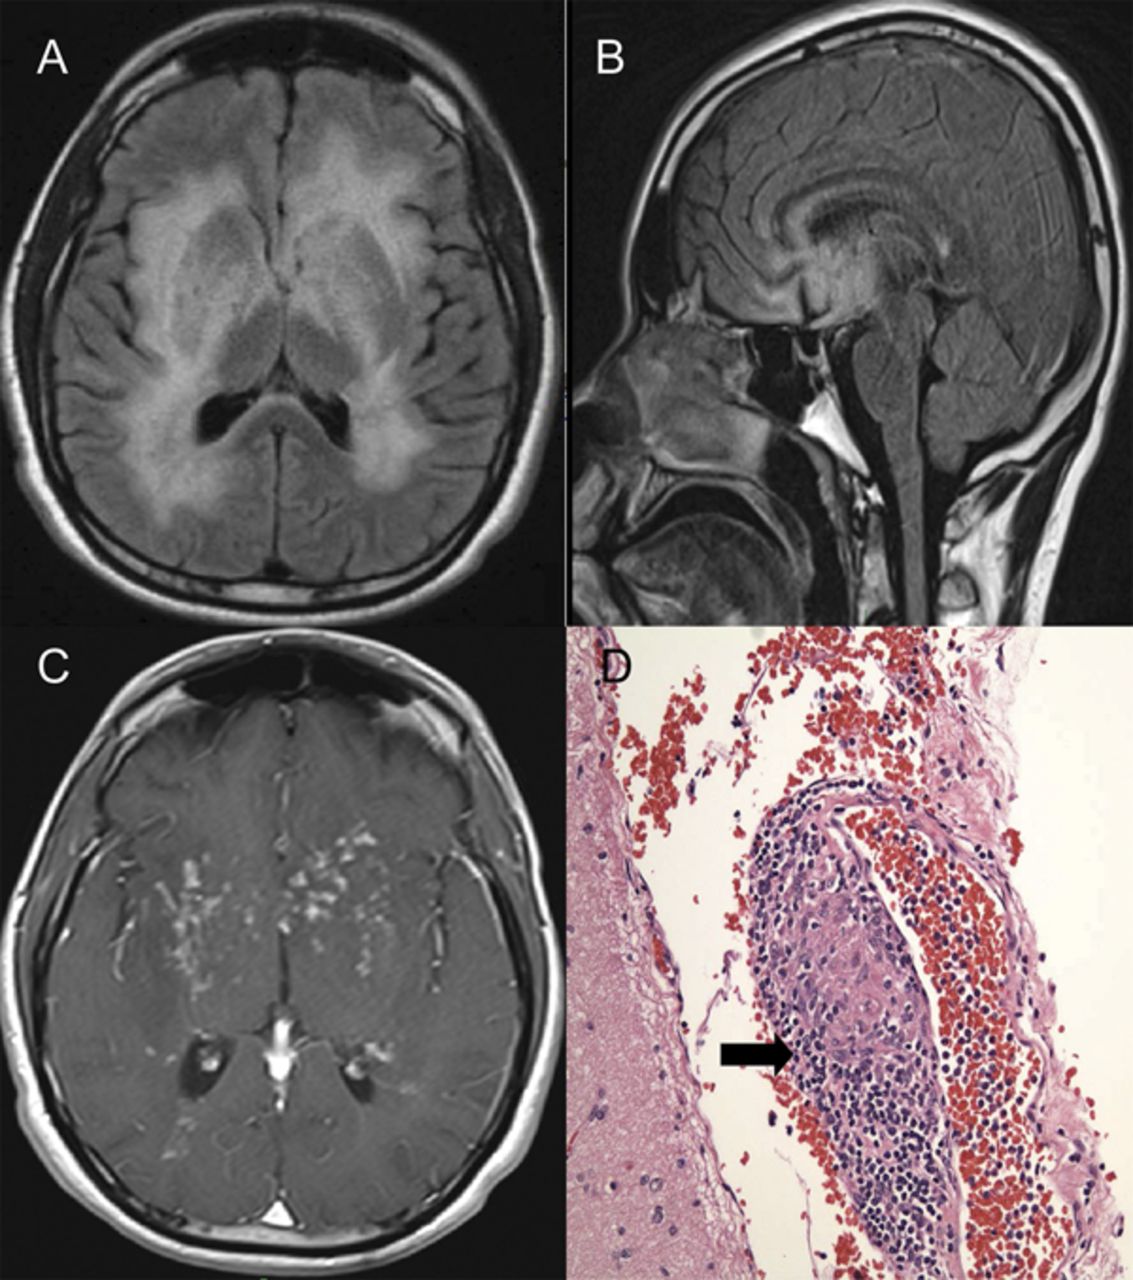

30岁的男人有躁郁症病史的疾病提供6个月的认知能力下降,步态蹒跚,尿潴留,双边上肢震颤。多个点状的增强病变被认为对大脑核磁共振(图)。鉴别诊断包括感染(病毒、结核或隐球菌)、有毒的脑白质病,神经胶质过多大脑,angiocentric淋巴瘤、神经。艾滋病毒检测,胸部CT扫描,CSF研究肝炎面板,屏幕药物,和血管炎面板是负的。脑活检显示神经。病人回答第四大剂量类固醇和环磷酰胺。MRI在神经往往揭示了加强室周的白质病变,在这种情况下模拟扩散神经胶质过多大脑。1,2

成像和组织学研究

(A) MRI轴fluid-attenuated反转恢复(天赋)序列显示广泛的室周的白质,和基底神经节hyperintensities。(B)矢状天赋展示语料库胼胝体的hyperintensity。(C)超声造影T1显示多个点状的加强皮层下白质病变显示感染或恶性肿瘤。(D)苏木精和伊红染色显示肉芽肿性炎症(箭头所指),符合神经。